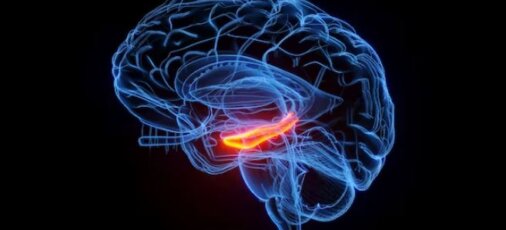

Της Rachael Elward, Senior Lecturer, Neuroscience and Neuropsychology, London South Bank University. Πηγή: The Conversation. Ίσως ξέρετε την ταινία κινουμένων σχεδίων Finding Nemo [...]